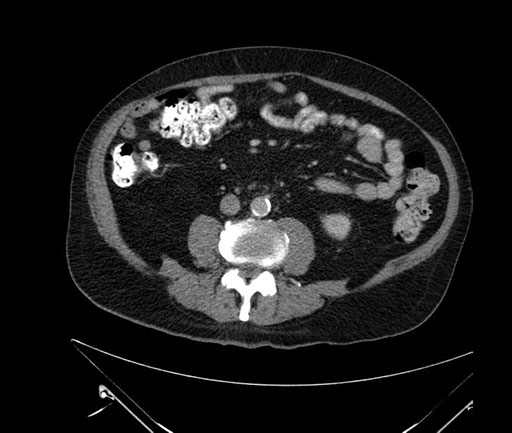

Imaging Analysis

Look through the patient's CT scan to identify any areas of concern for the necessary procedure.

Based on your CT findings, which issue(s) would give reason for "planned slowing down moment(s)" in this case?

Considering a standard Whipple procedure, what step(s) of the operation would you do differently in this case?